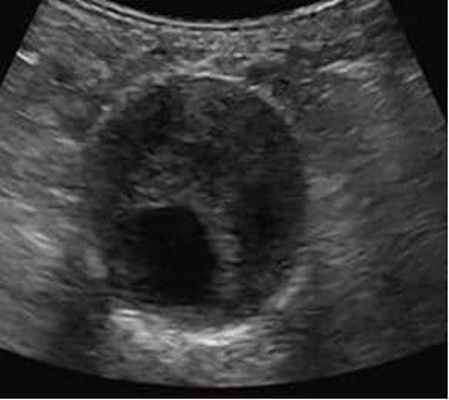

Ультразвуковое дуплексное исследование – "золотой стандарт" скринингового обследования пациентов (обнаружение и динамическое наблюдение);

Аневризма брюшной аорты - это локальное или диффузное расширение диаметра брюшного отдела аорты более 3 см. Истончение стенки и развитие аневризмы аорты в основном носит приобретенный характер и обусловлено атеросклерозом в 95% случаев, на остальные причины (неспецифический аортоартериит, туберкулезное, сифилитическое, ревматическое поражение аорты) приходится всего 5%.

Примерно в четверти случаев аневризма брюшной аорты развивается абсолютно бессимптомно и обнаруживается случайно, при УЗИ либо рентгеновском исследовании брюшной полости. Если же заболевание не обнаружено вовремя, высока вероятность внезапного разрыва аневризмы, что внешне сопровождается внезапной бледностью и потерей сознания. Жизнь больного при разрыве аневризмы зависит от того, насколько быстро он будет доставлен в больницу и попадёт на операционный стол.